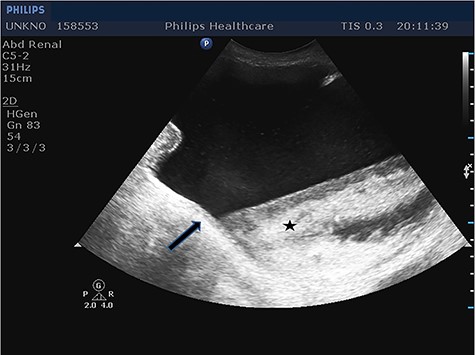

Given the fact that the patient was still hemodynamically stable, and in order to identify preoperatively the content of the incarcerated hernia sac, prompt imaging with ultrasound was considered necessary. Imaging revealed the protrusion of the entire bladder through the right internal inguinal ring and extending into the scrotum (Fig. 1), as well as hydronephrosis of the right kidney (Fig. 2), justifying the patient’s renal dysfunction.

Longitudinal ultrasound image of the inguinal canal revealed a hernia that contained the entire urinary bladder. Notice the urothelium (arrow), as well as a great amount of debris (star).